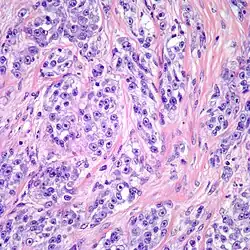

W obrazie mikroskopowym utkanie guza tworzą gęste gniazda lub pęczki komórek wrzecionowatych lub poligonalnych pooddzielane przegrodami łącznotkankowymi. Komórki o wrzecionowatym lub wielobocznym kształcie są wyraźnie odgraniczone, posiadają obfitą jasną lub słabo eozynofilną cytoplazmę z pęcherzykowym jądrem i wydatnym bazofilnym jąderkiem[2][9]. Aktywność mitotyczna jest niska, podobnie stopień pleomorfizmu jest niewielki. W około połowie guzów obecne są wielojądrowe komórki olbrzymie oraz ogniska melaniny[2].

Materiał pobrany podczas biopsji lub preparat pooperacyjny jest barwiony i oceniany pod mikroskopem. W obrazie mikroskopowym obecne są komórki wrzecionowate lub poligonalne o jasnej cytoplazmie ułożone w gęste gniazda lub tworzące pęczki[6][29].